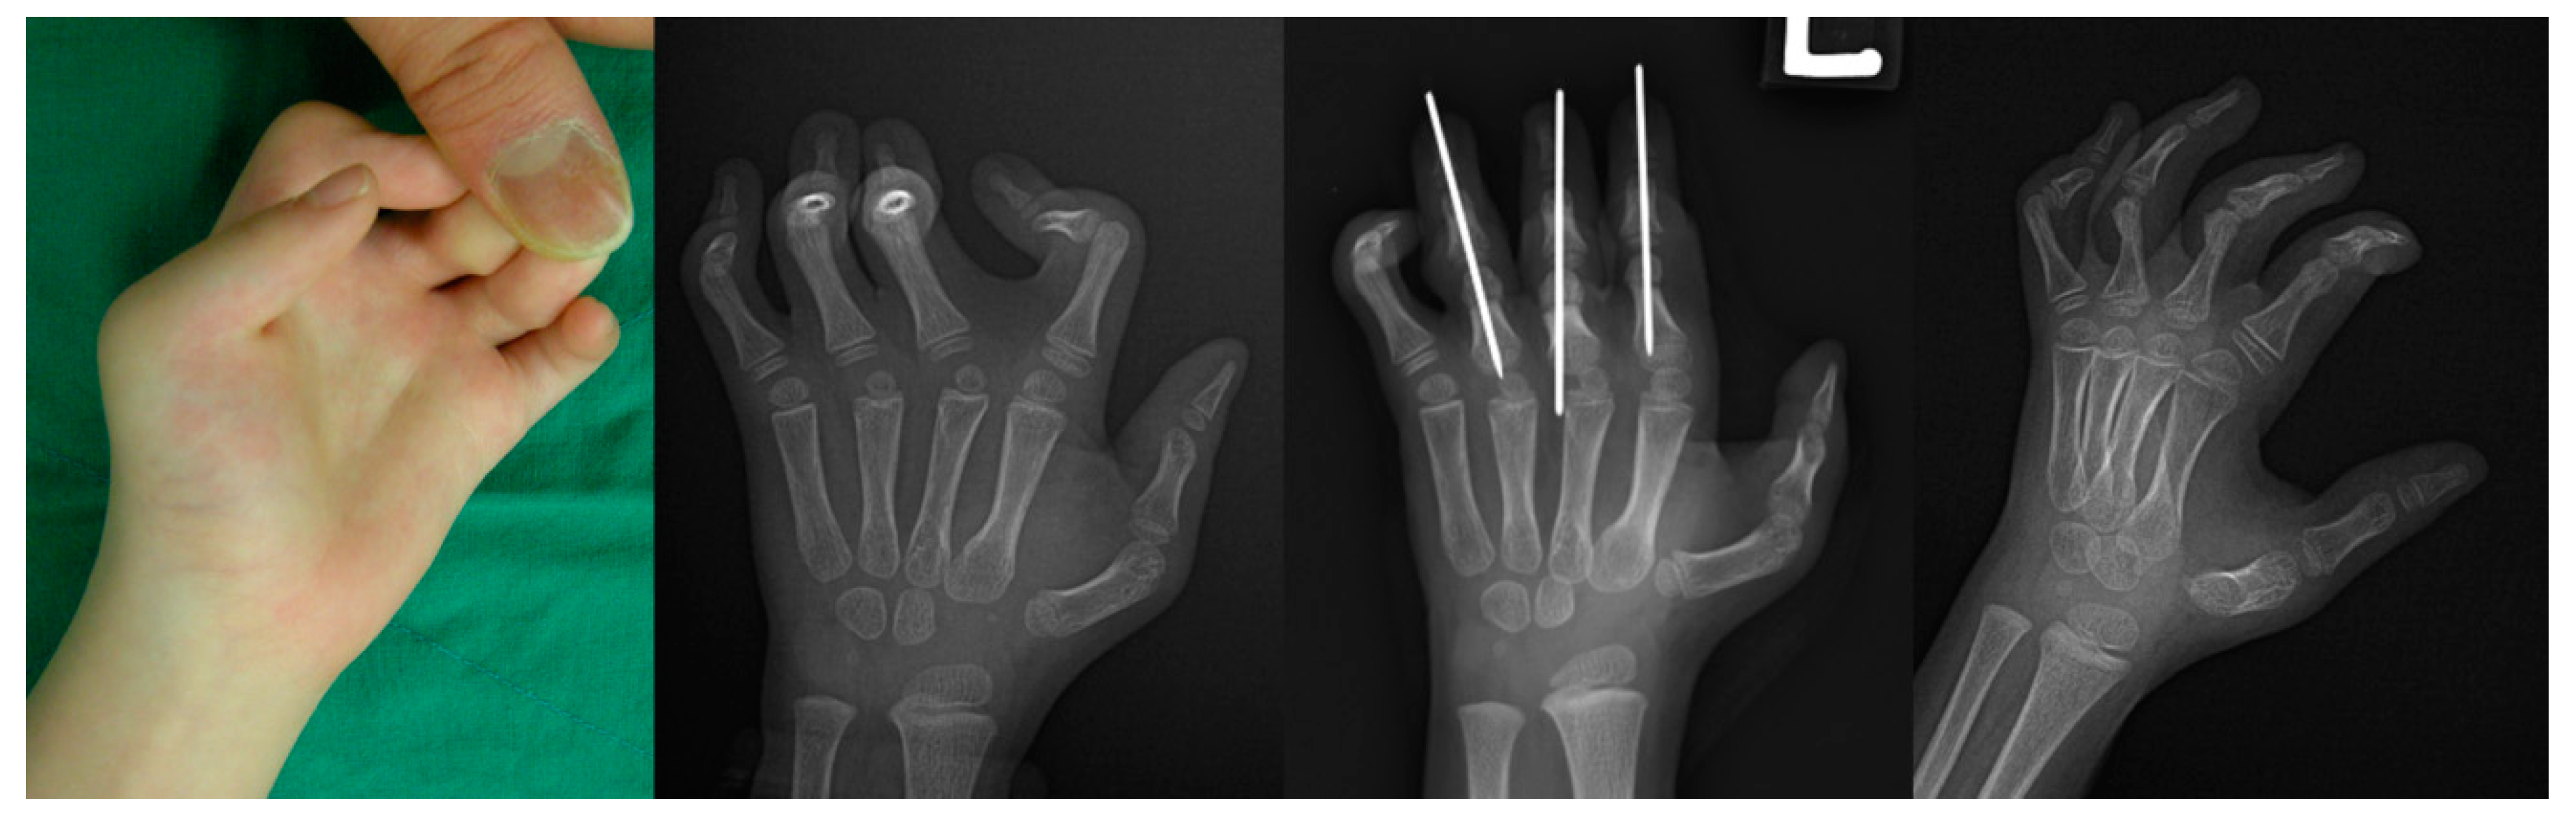

Complicated surgical techniques involving various structures prolong the duration of surgery, which can increase the risk of postoperative infection and surgical wound issues [21]. Furthermore, syndromic camptodactyly frequently involves multiple digits, and a bloodless and straightforward surgical technique with a short operative time would be proper. It is hard to correct flexion deformities involving multiple digits in less than 2 h, which is accepted as the safe limit for tourniquet application [22]. While none of the previous studies described the surgical duration for performing soft tissue release, an osteotomy does not require a long incision, soft tissue reconstruction, or skin grafting, so we can easily expect a shorter surgery. In this study, the mean duration of surgery from incision to closure was only 25.8 min per finger. This technique can thus be performed in a shorter time than soft tissue release and is suitable for surgery on multiple fingers in patients with syndromic camptodactyly (Figure 5).

Figure 5. The clinical image and radiographs of an arthrogryposis patient with syndromic camptodactyly show the flexion contractures from second to fifth finger with the left hand’s thumb-in palm deformity. Despite the restricted wrist motion with the lack of wrist crease, the patient did not present the flexion contracture of the wrist but complained of discomfort when grasping objects such as cups. After the correction of camptodactyly via one-stage extension shortening osteotomies, the hand function improved with the proper bony union.